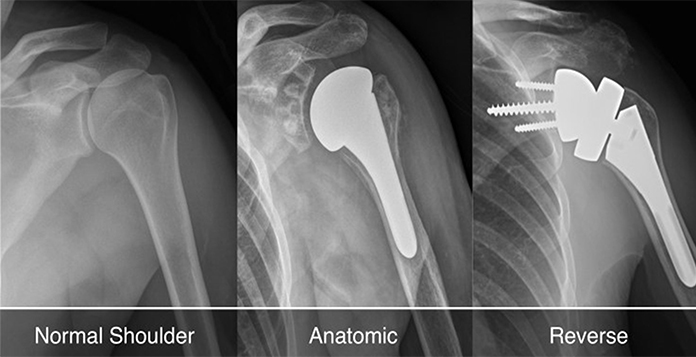

A shoulder surgery involves the initial assessment of your condition, following certain diagnostic tests and screenings to determine the severity of the condition. This will help your surgeon to decide which type of shoulder arthroplasty will be suitable in your case. The three traditional types of a shoulder arthroplasty are:

1. Total Shoulder Arthroplasty – A total shoulder replacement involves the ball on top of the upper arm (humerus) being replaced with a metal prosthesis, and the socket is covered with a plastic surface. Also, a total shoulder arthroplasty is the most common type of shoulder surgery.

2. Partial Shoulder Arthroplasty – A partial shoulder arthroplasty involves only the ball of the joint being replaced, which is a smaller surgery as compared to the other types.

3. Reverse Shoulder Arthroplasty – This is usually done when you have a rotator cuff tear. Apart from that, it is also done as a correction to a previous shoulder surgery that probably did not work. A reverse shoulder surgery involves the ball being attached to the shoulder bones, and the socket is attached from the top of your upper arm.